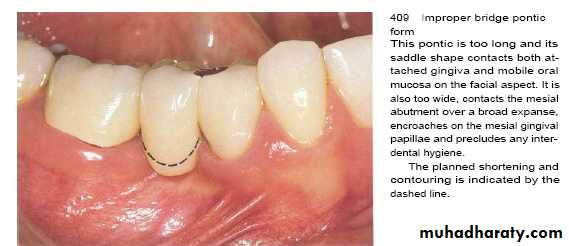

The undersurface of pontics in fixed bridges should barely touch the mucosa.

Access for oral hygiene is inhibited with excessive pontic contact to tissue which can leads to plaque accumulation and pseudpocket.Crown Contour

• Restorations contour is extremely important to the maintain periodontal health.• Ideal contour provides

• Access for hygiene

• The fullness to create the desired gingival form

• Pleasing visual tooth contour in esthetic areas

The most frequent cause of overcontoured restorations is inadequate tooth preparation by the dentist, which forces the technician to produce a bulky restoration to provide room for the restorative material.

In areas of the mouth where esthetics are not critical, a flatter contour is always acceptable.

Contour of artificial crown or bridge or restoration should be cleansable so as to decrease plaque retention & gingival inflammation .